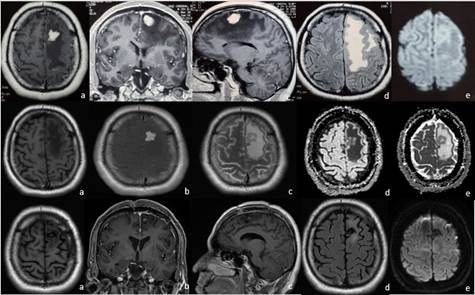

Figura 1 Resonancia magnética encefálica al ingreso, pre operatorio y a 6 meses postoperatorio (1°, 2da y 3era fila respectivamente). En la 1ª fila (a,b,c) imagen T1 contrastada, se aprecia un realce homogéneo frontal izquierdo en corte axial coronal y sagital; (d) con edema asociado en FLAIR y (e ) sin restricción a la difusión aparente. 2da fila: imagen en T1, T1 con contraste y FLAIR (a,b,c); Difusión y ADC sin restricción aparente (d,e). 3ra fila: hipointensidad frontal izquierda en relación a resección de masa tumoral; no realce al contraste (b,c), leve edema perilesional en FLAIR (d).